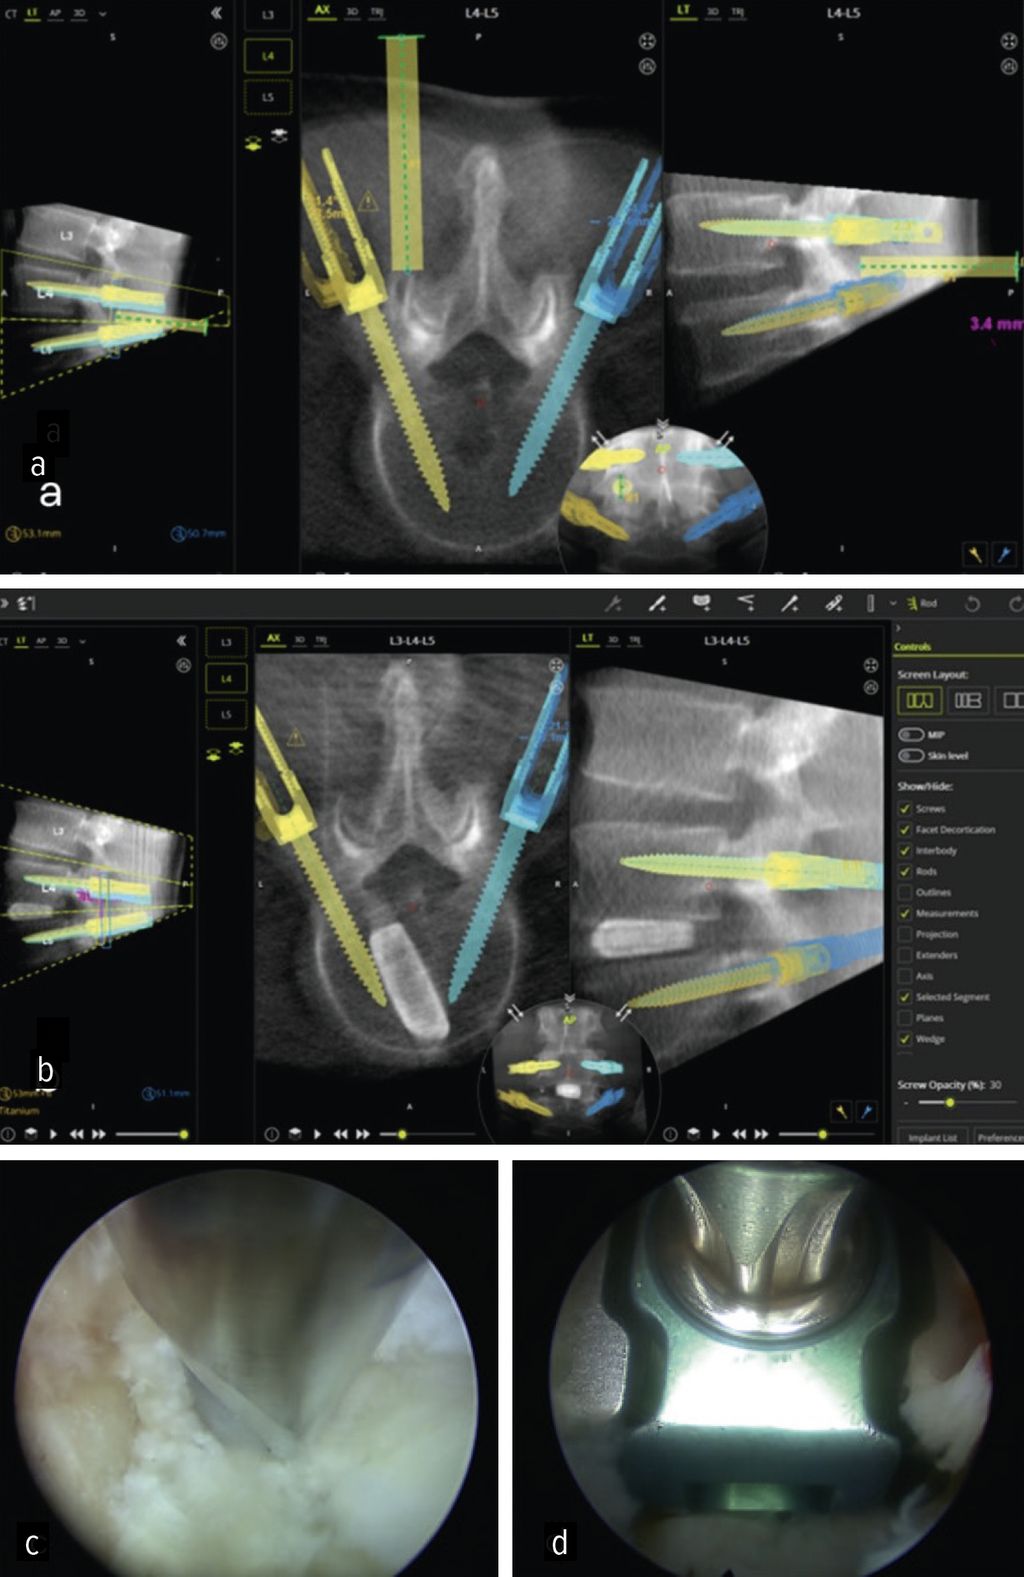

Die minimalinvasive transforaminale lumbale interkorporelle Fusion (Minimally Invasive Transforaminal Lumbar Interbody Fusion; MIS-TLIF) hat in den letzten Jahren an Bedeutung gewonnen, die aufgrund des geringeren Gewebetraumas mit einer früheren Rekonvaleszenz verbunden ist.24 Aus den gleichen Gründen rückt die endoskopische transforaminäre InterbodyFusion (Endo-TLIF) in den Fokus der Aufmerksamkeit. Endo-TLIF ist eine Erweiterung der MIS-TLIF und erfordert eine unilaterale Resektion des Facettengelenkes. Die Grund- und Deckplattenpräparation gilt als entscheidender Faktor, der die Fusionsrate beeinflusst.24 Die Möglichkeit, unter klarer endoskopischer Sicht die Endplatten präzise darzustellen, erlaubt eine ideale Aufbereitung des Fusionsbettes. Dies könnte zu einer Erhöhung der Fusionsrate beitragen. Zudem profitieren die Patienten durch eine raschere Erholung, einen geringeren Opioidbedarf, eine frühzeitige Mobilisierung und eine verkürzte stationäre Verweildauer.25 Limitationen liegen aktuell bei höhergradigen Listhesen und kollabierten Bandscheibenräumen vor.26 Um das Potenzial der Methodik zu untermauern, bedarf es robuster Studien mit erhöhtem Evidenzlevel sowie eines einheitlichen Standards der endoskopischen Fusionstechniken. Abbildung 6 zeigt eine Planungsanwendung (MazorX® Application, Fa. Medtronic) für Endoskoptrajektorie und Pedikelschraubenimplantation im Rahmen der Endo-TLIF-Operation (a, b). Abbildung b zeigt einen oblique eingebrachten Cage (eFuse® expandable, Fa. Evospine), Abbildung c einen Nukleusresektor (Fa. RIWOspine) bei Präparation des Fusionsbettes. Abbildung d zeigt, dass eine Cagedistraktion unter direkter Sicht möglich ist.

Höhere Genauigkeit, kürzere Krankenhausaufenthalte und geringere Strahlenexposition sind die Gründe für den Einsatz bei der Pedikelschrauben-Implantation.32 Zusätzlich bieten sie den Vorteil der exakten physischen Führung, um präoperativ geplante chirurgische Trajektorien in der Endoskoppositionierung umzusetzen. Wang et al. setzten robotische Assistenz bei vollendoskopischen lumbalen Diskektomien ein und konnten Sicherheit und Effektivität als Alternative zur konventionell fluoroskopischen ESS bestätigen.38 Im eigenen Haus wurde das Verfahren bei der endoskopischen TLIF-Operation angewandt.